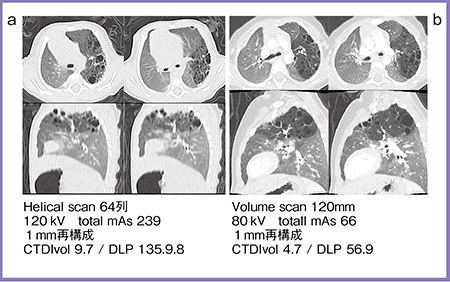

2.先天性気管支閉鎖症

症例2は,胎児診断されていた先天性気管支閉鎖症の症例である。日齢3に施行された64列CTによる検査で緊急の手術は不要と判断され,8か月後に再度320列ADCTで検査を行っている(図2)。成長して構造が大きくなっていることもあるが,図2bでは画質が向上して非常に鮮鋭な画像を得られており,区域気管支までを十分に評価できる。呼吸による影響が多少あるが,肺血管や気管支の構造,葉間を評価することも可能である。

ADCTでは先天性肺疾患に多い分葉の異常を術前情報として取得でき,ボリュームスキャンにより横隔膜付近もボケのない鮮鋭な画像を低線量で得られるようになった。

図2 症例2:先天性気管支閉鎖症(胎児診断例)

a:Aquilion 64で撮影した日齢3,2.7kgの画像

b:Aquilion ONEで撮影した8か月,8kgの画像